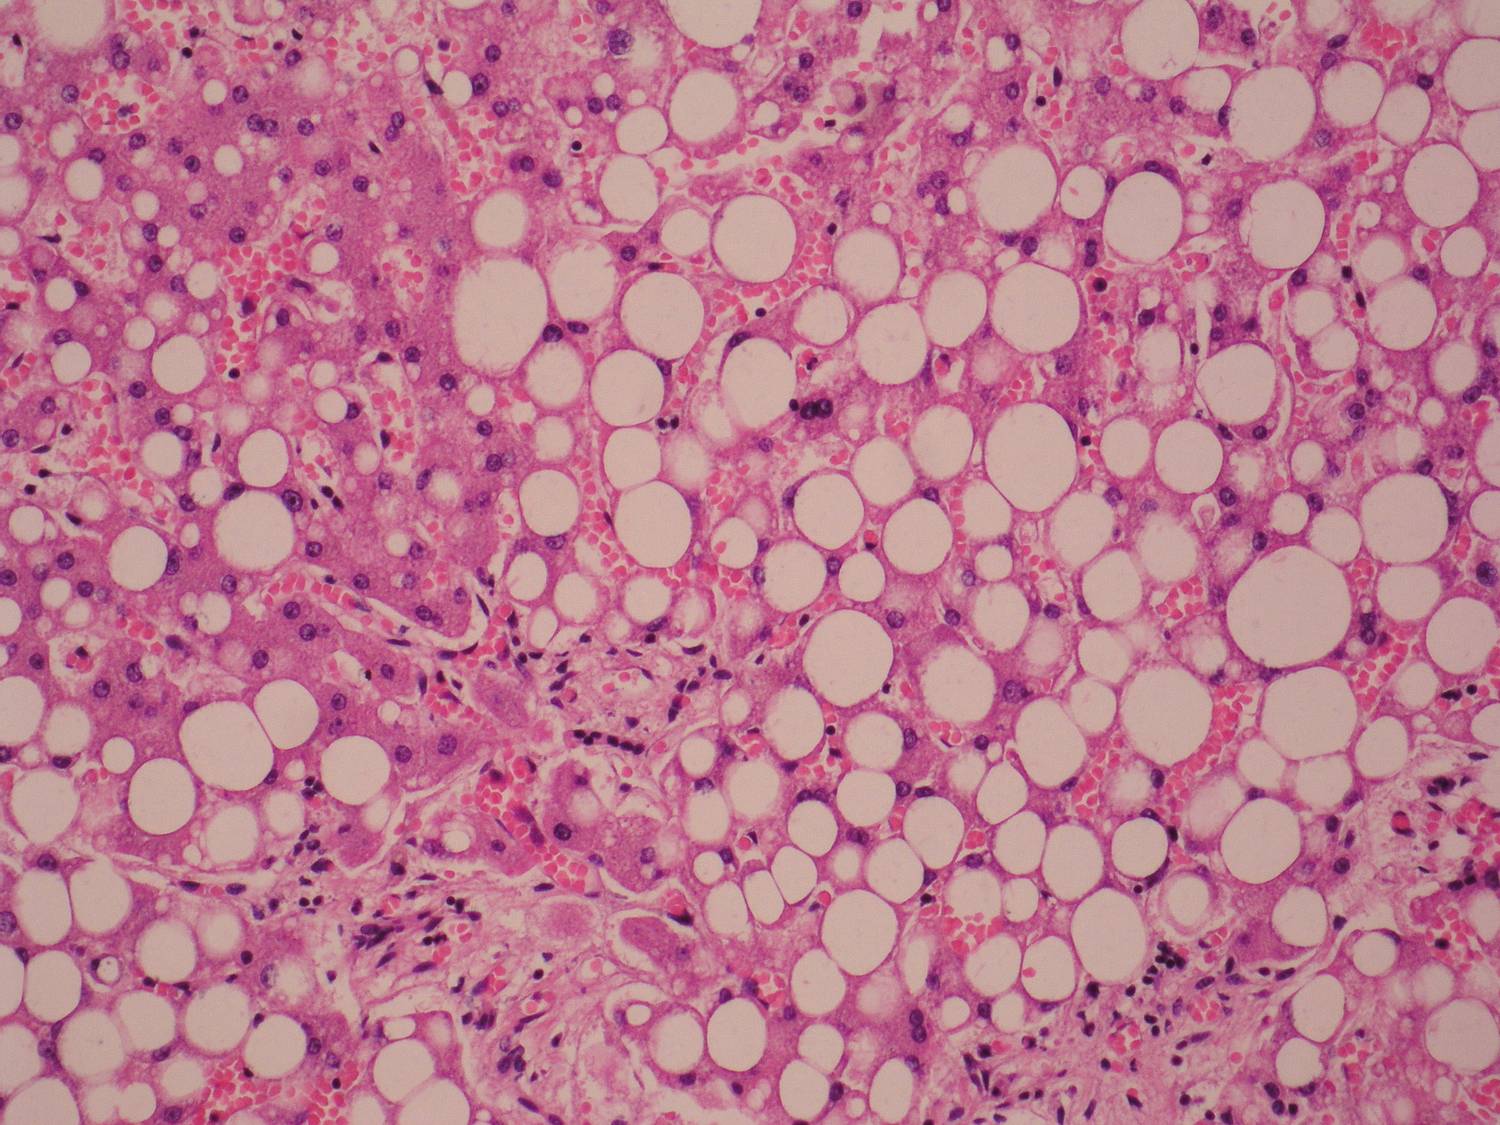

Диффузный стеатоз что это